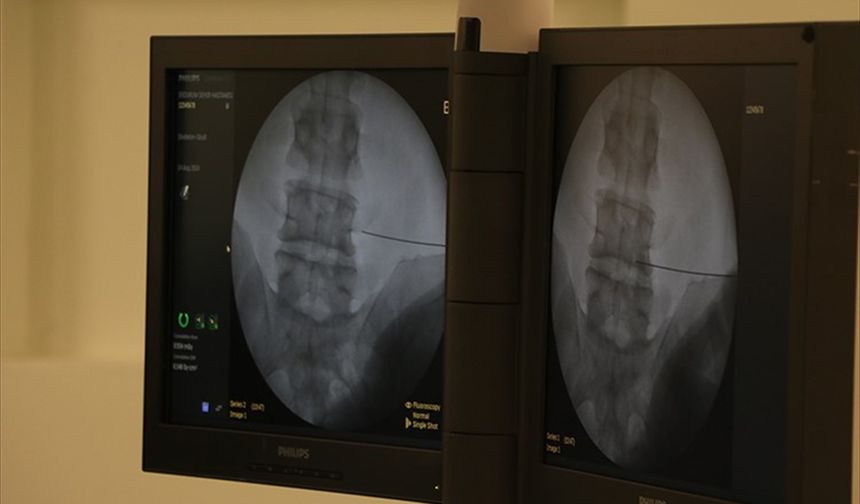

Bitlis'te 66 yaşındaki hasta kapalı yöntemle yapılan omurga ameliyatıyla sağlığına kavuştu